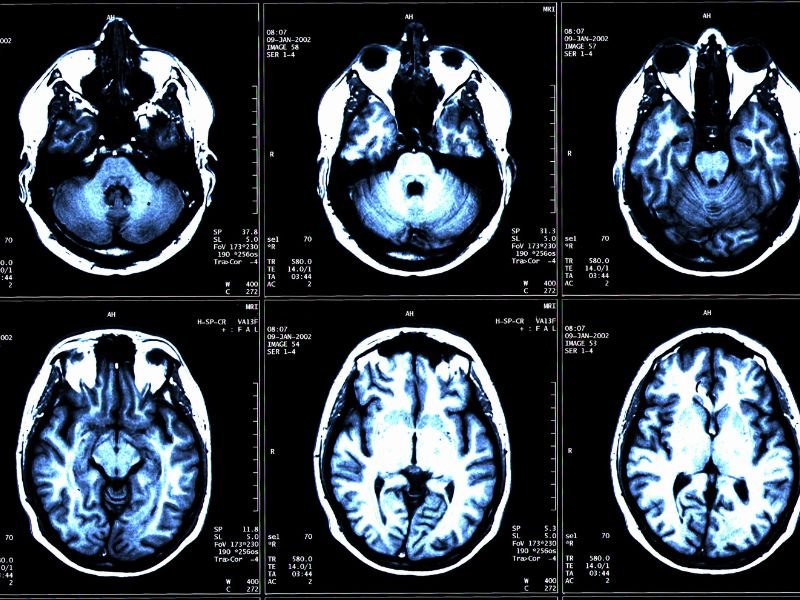

Infiltração para Dor de Cabeça em Criciúma A dor de cabeça é uma condição comum que pode afetar significativamente a qualidade de vida de uma pessoa. Em Criciúma, muitos pacientes buscam soluções para aliviar esse